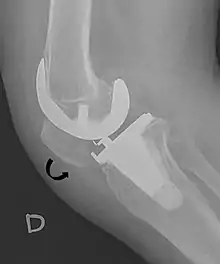

The Insall-Salvati ratio helps to indicate patella baja on lateral X-rays, and is calculated as the patellar tendon length divided by the patellar bone length. An Insall-Salvati ratio of < 0.8 indicates patella baja.[6]

- Melloni, Pietro; Veintemillas, Maite; Marin, Anna; Valls, Rafael (2013). "Imaging Patellar Complications After Knee Arthroplasty". Arthroplasty - Update. doi:10.5772/53666. ISBN 978-953-51-0995-2. (CC-BY-3.0)